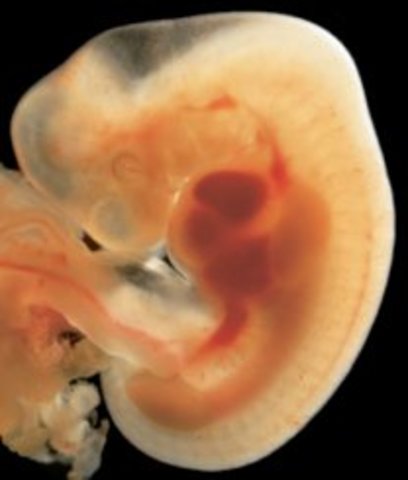

• Week 6

Week 6

Embryo becomes 1/4 inch, spinal cord begins to close, first blood cells and blood vessels develop, heart is formed and begins beating, brain develops into 5 parts, optic cavaties and appendage cells are in place to be developed.

• Week 7

Week 7

Embryo is now 1/2 inch, heart beats with 1 chamber, arms and legs begin to grow, jaw and vocal cords begin forming the lungs, the liver, the pancreas, and the thyroid gland begin forming.